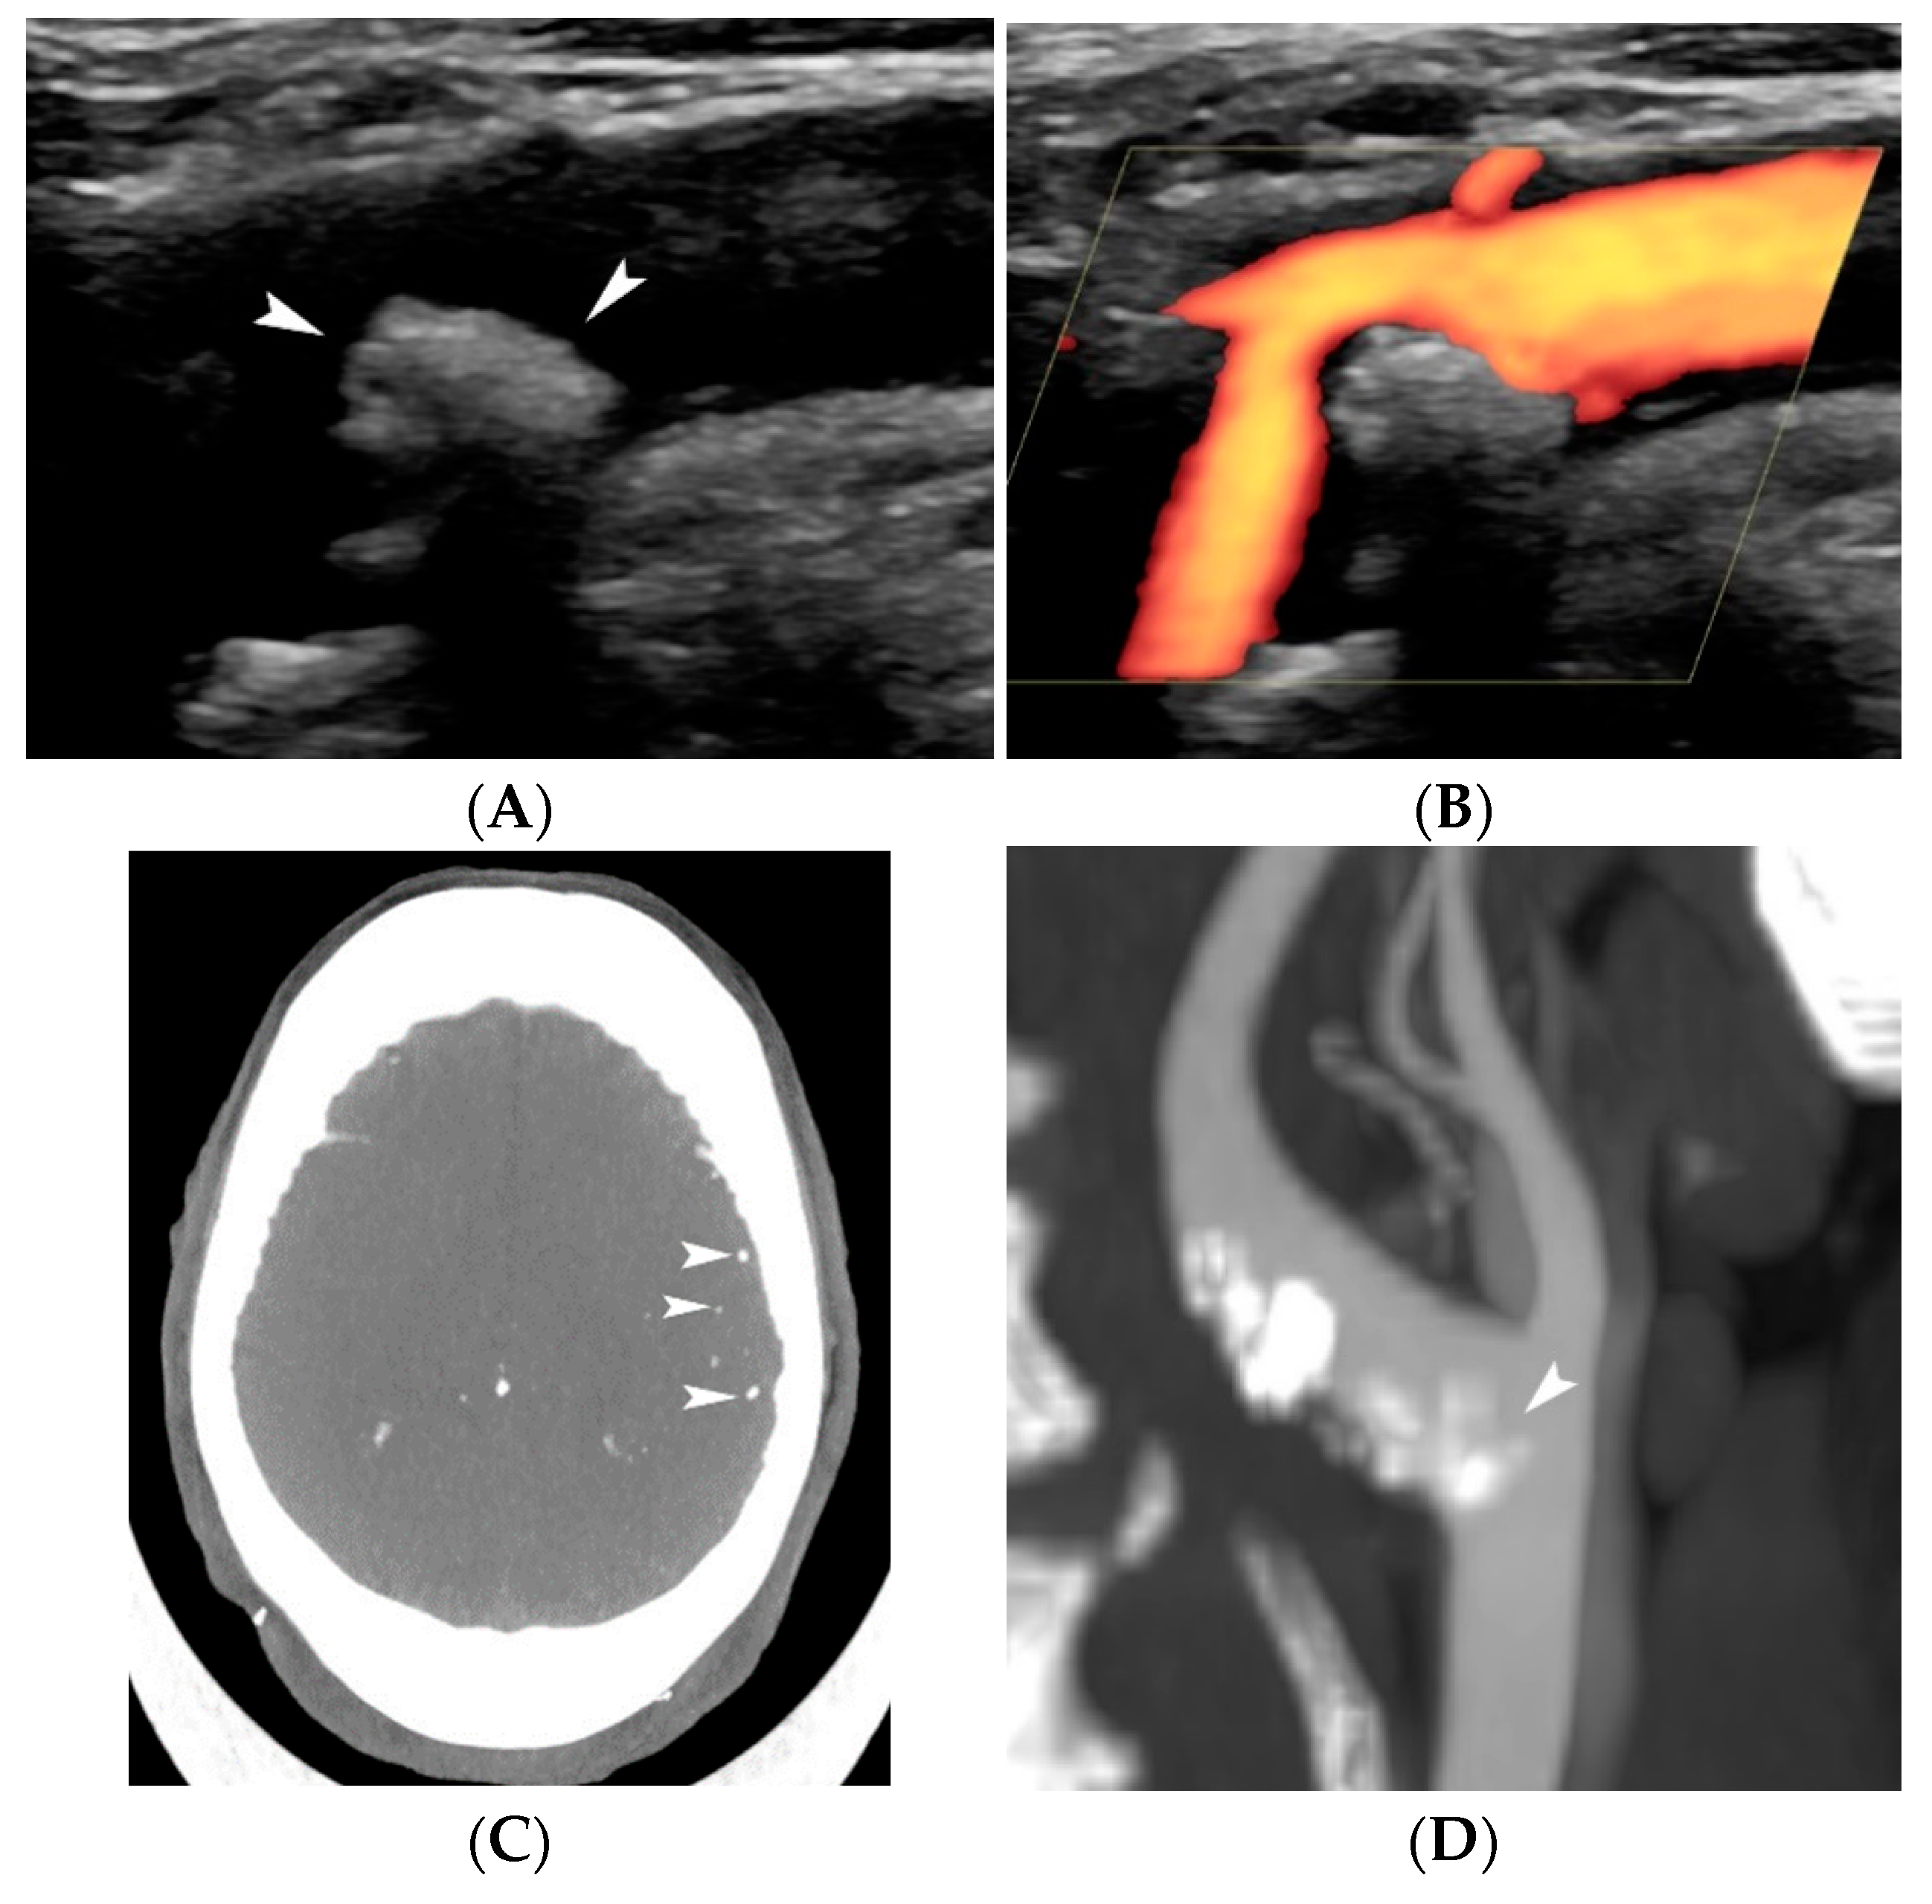

4.1.4. Plaque Ulceration

- Rafailidis, V.; Chryssogonidis, I.; Tegos, T.; Kouskouras, K.; Charitanti-Kouridou, A. Imaging of the ulcerated carotid atherosclerotic plaque: A review of the literature. Insights Imaging 2017, 8, 213–225. [Google Scholar] [CrossRef]

- Hamada, O.; Sakata, N.; Ogata, T.; Shimada, H.; Inoue, T. Contrast-enhanced ultrasonography for detecting histological carotid plaque rupture: Quantitative analysis of ulcer. Int. J. Stroke 2016, 11, 791–798. [Google Scholar] [CrossRef] [PubMed]

- ten Kate, G.L.; van Dijk, A.C.; van den Oord, S.C.; Hussain, B.; Verhagen, H.J.; Sijbrands, E.J.; van der Steen, A.F.; van der Lugt, A.; Schinkel, A.F. Usefulness of contrast-enhanced ultrasound for detection of carotid plaque ulceration in patients with symptomatic carotid atherosclerosis. Am. J. Cardiol. 2013, 112, 292–298. [Google Scholar] [CrossRef] [PubMed]

- Rafailidis, V.; Charitanti, A.; Tegos, T.; Rafailidis, D.; Chryssogonidis, I. Swirling of microbubbles: Demonstration of a new finding of carotid plaque ulceration on contrast-enhanced ultrasound explaining the arterio-arterial embolism mechanism. Clin. Hemorheol. Microcirc. 2016, 64, 245–250. [Google Scholar] [CrossRef]

- Rafailidis, V.; Chryssogonidis, I.; Xerras, C.; Nikolaou, I.; Tegos, T.; Kouskouras, K.; Rafailidis, D.; Charitanti-Kouridou, A. A comparative study of color Doppler imaging and contrast-enhanced ultrasound for the detection of ulceration in patients with carotid atherosclerotic disease. Eur. Radiol. 2019, 29, 2137–2145. [Google Scholar] [CrossRef]